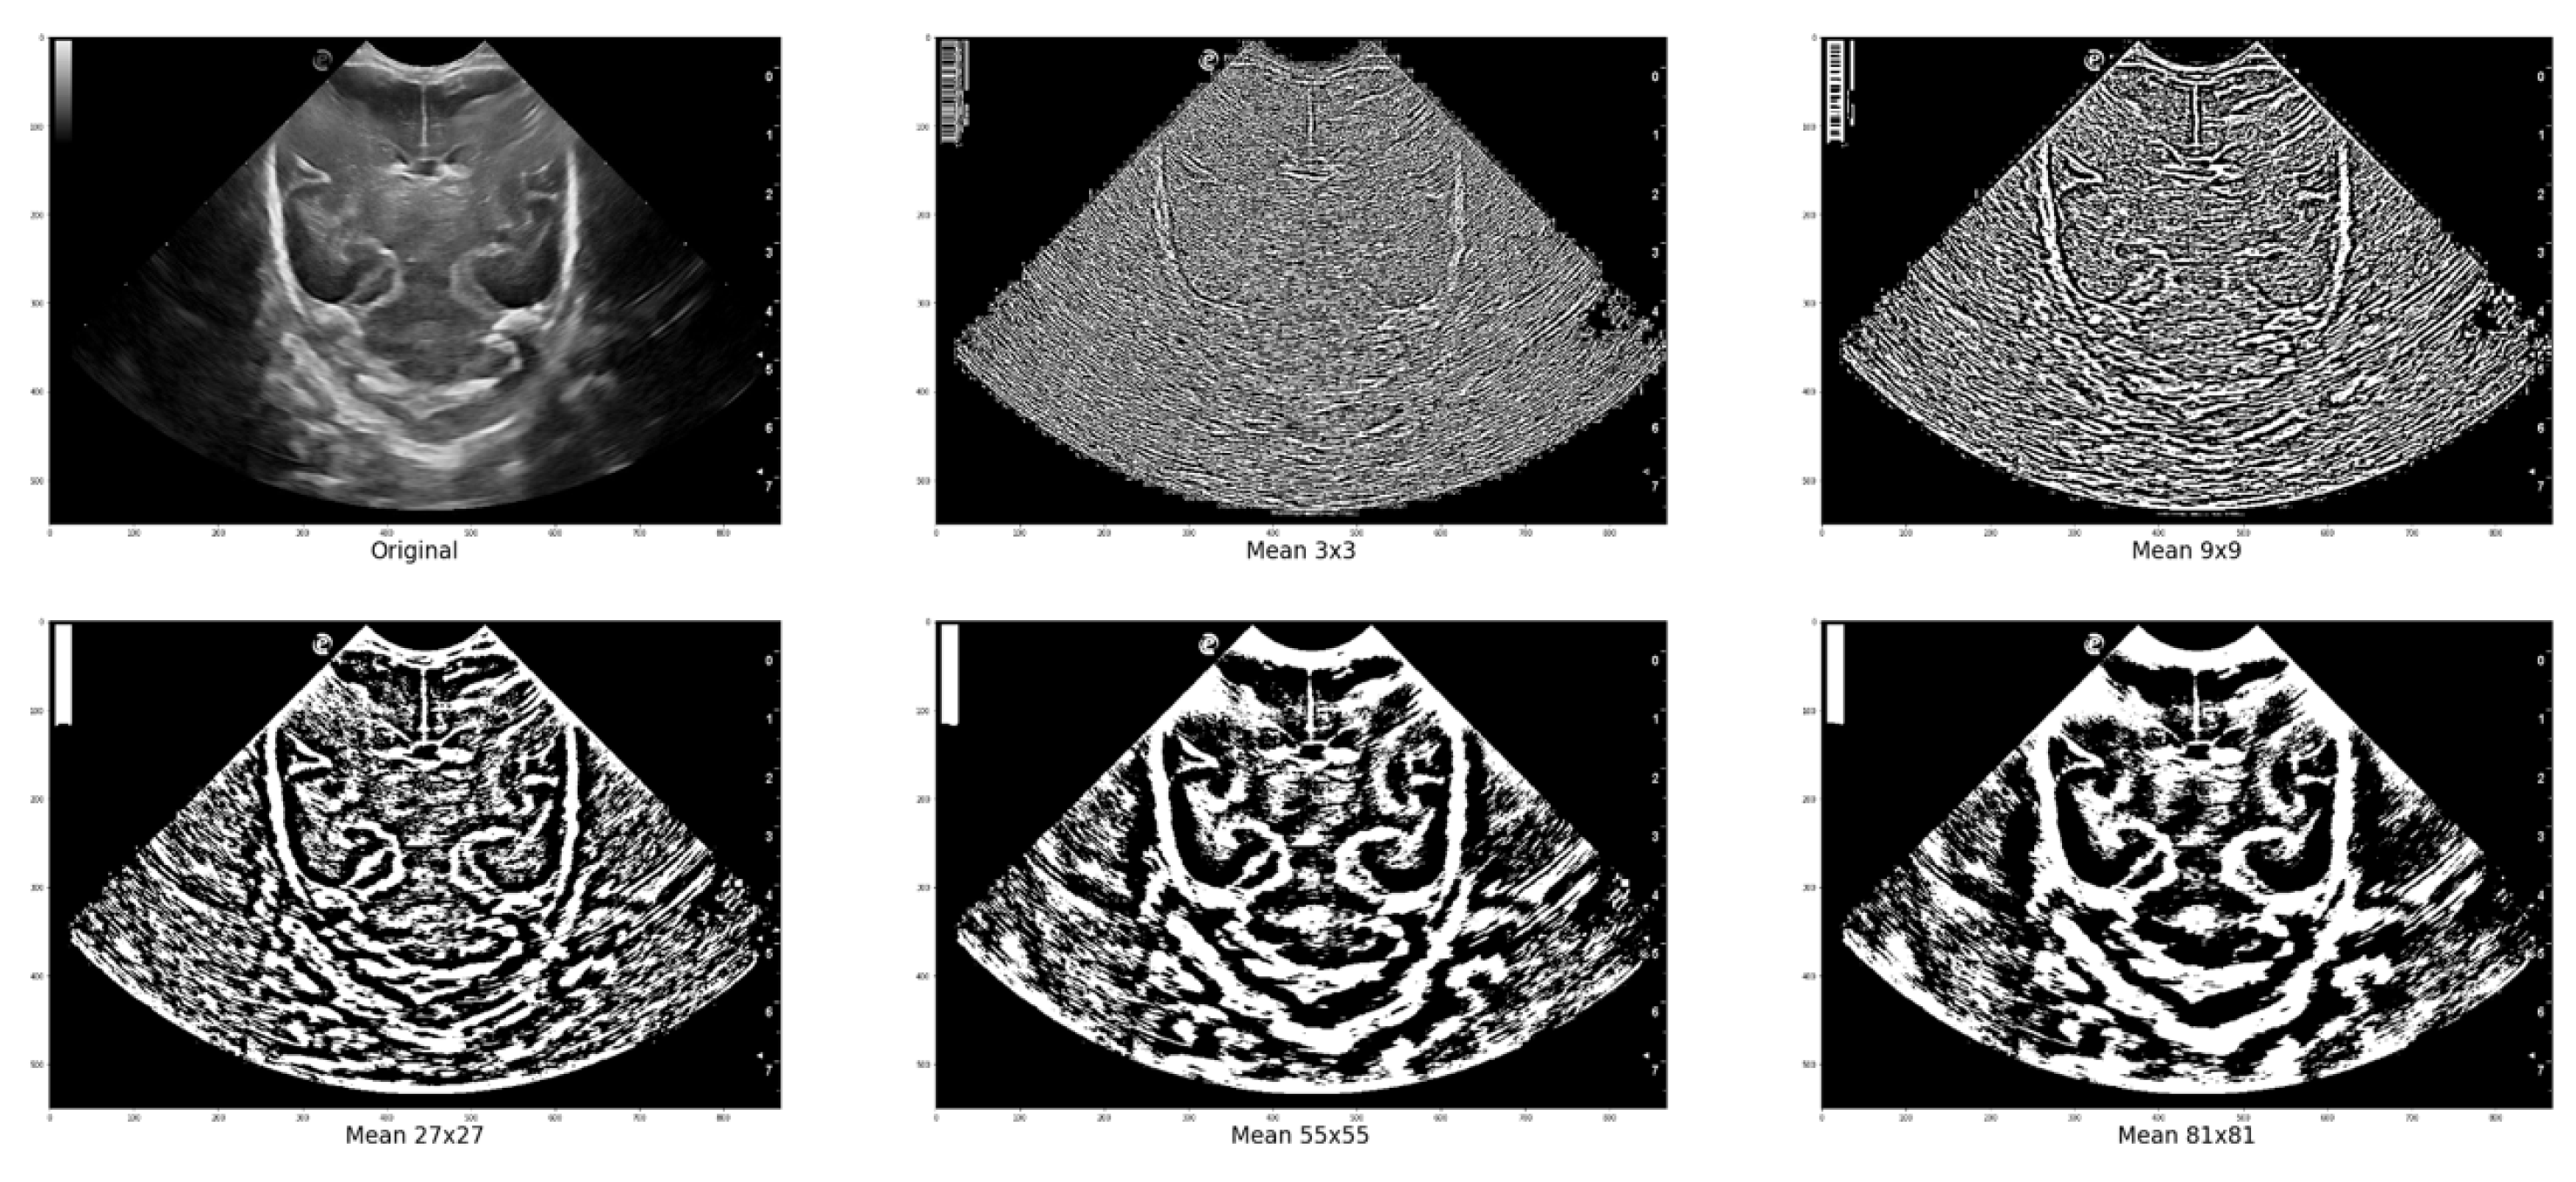

2.3. Methodology structure and implementation

In grayscale images, the intensity increases as the pixel value approaches 255, which represents white. This value is determined by the fact that each pixel is represented by an 8-bit binary value, which, when converted to decimal, can range only from 0 to 255. The platform utilizes the Local Thresholding method to account for the noise and undefined areas commonly present in ultrasound images. This method involves selecting regions ( b l o c k _ s i z e ) around each pixel in the input image to determine its value based on a defined method and parameter ( p a r a m ). In the "Gaussian" method, a specific sigma value is utilized, whereas in the "generic" method, a function object is employed to calculate the threshold for the center pixel. This calculation is based on the flat matrix of the local neighborhood, as specified in Equation 1.

Figure 5 displays various images where local thresholding was performed on different regions. The images show how regions with greater intensity are distinct and separated from other areas where there are no grooves or bones.

Figure 5. Local Filter has been applied to an ultrasound image (Original) with different surface sizes for analysis. As shown in the figure, the resulting images obtained using Mean 3x3, 9x9, 27x27, 55x55, and 81x81 pixels are presented from left to right as an example.